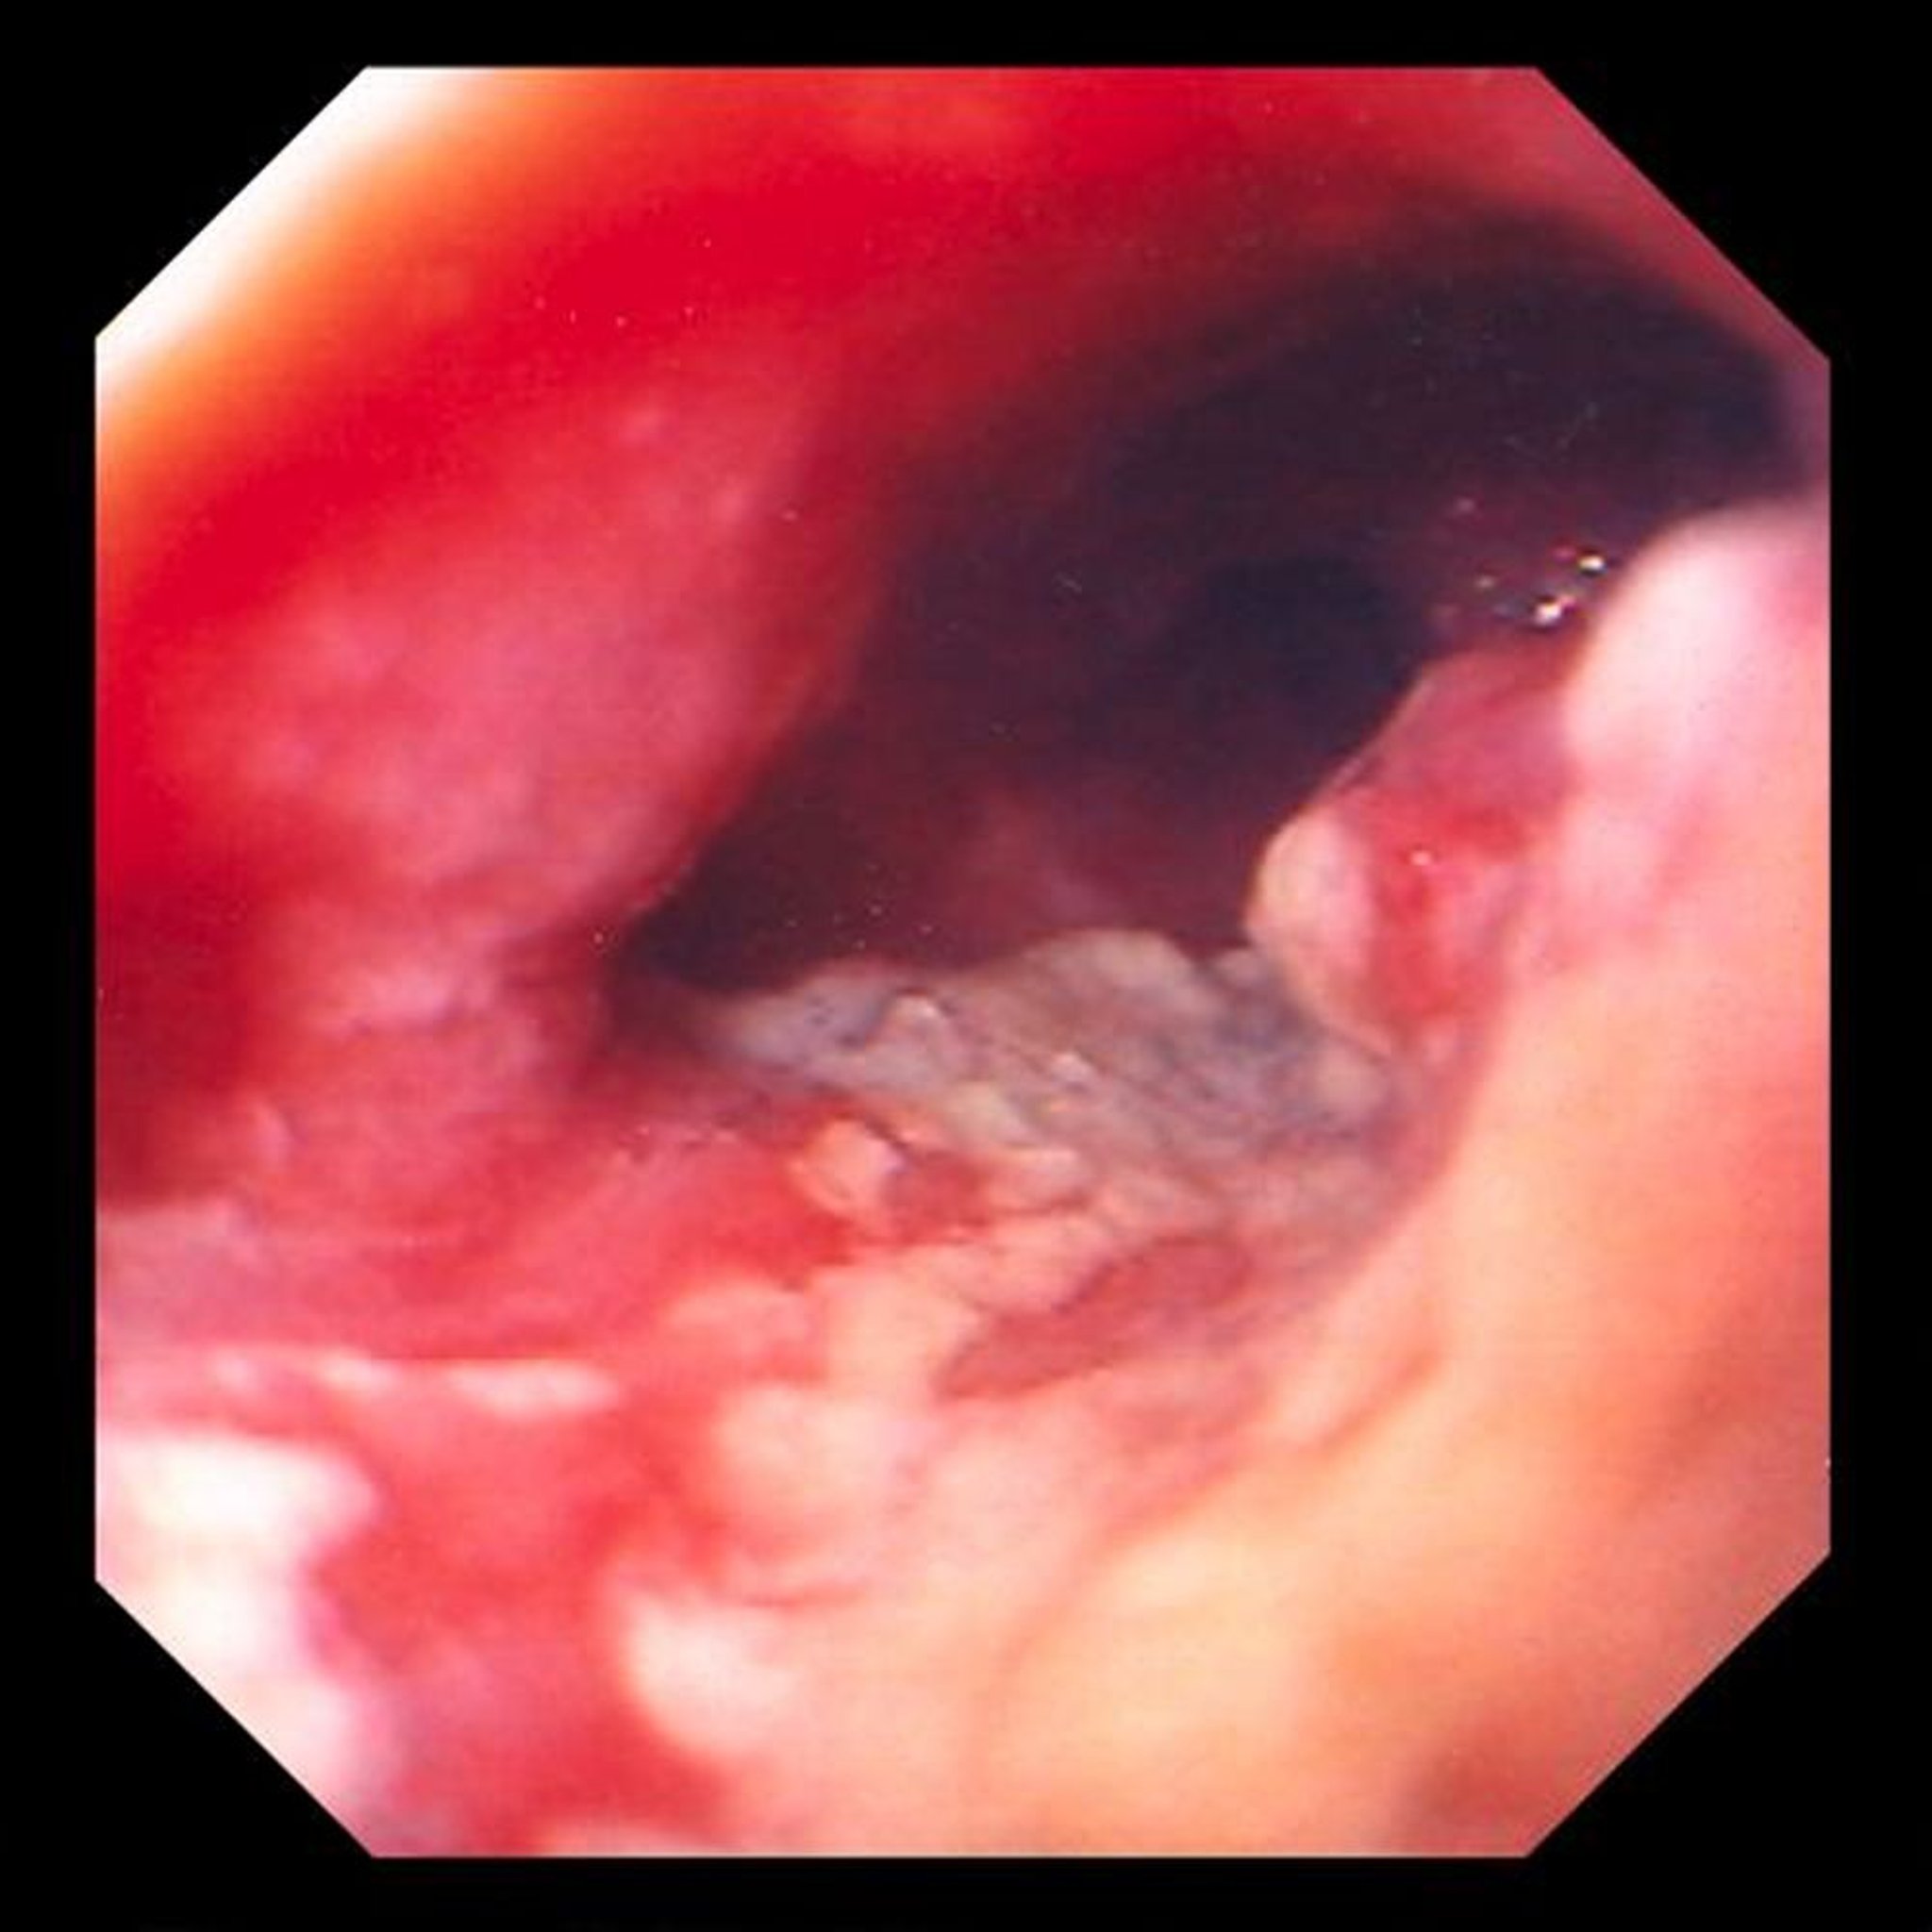

Adénocarcinome de l'œsophage

Cette image montre une tumeur ulcérée, constrictive située dans l'œsophage distal, très évocatrice d'un adénocarcinome résultant de modifications métaplasiques (épithélium colonnaire) (œsophage de Barrett).

Image provided by David M. Martin, MD.